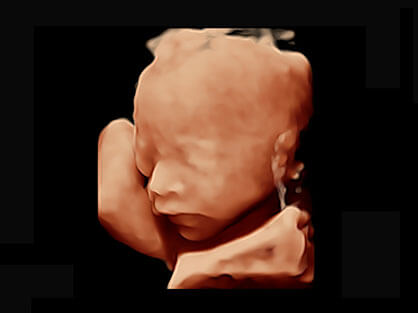

作为P系列家族成员之一,P40 Plus采用16877太阳集团高端超声系统平台——极光,并以时尚秀丽、小巧灵动的外观设计绽放出灵动之韵、科技之美。高端平台的使用保证了P40 Plus优质的基础图像;完备的高级功能可满足您全身应用的基本需求;丰富的探头配置、多样的高级4D成像及分析软件为您日益增多的妇产应用需求提供丰富的诊疗方案。

宽频带腹部凸阵探头和腹部容积探头、大角度腔内探头和腔内容积探头、独特的生殖专用曲柄探头,为妇产应用提供全面诊疗方案。